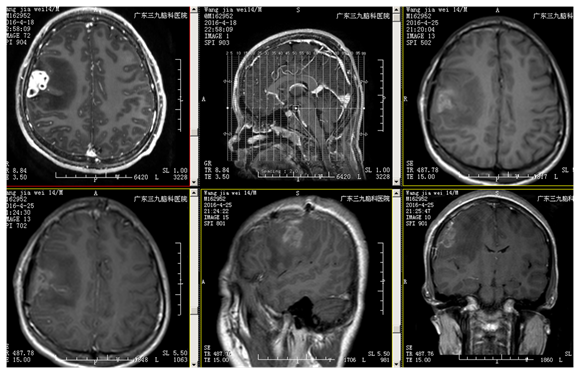

王某某,男,14岁,1年前发热及口角抽搐,在外院抗病毒、抗癫痫治疗,治疗效果不理想,近2周症状加重伴头晕头痛。外院MR:右额不规则异常强化(斑片状、环形强化),考虑感染性病变。既往外院实验室检查:脑脊液免疫球蛋白M0.357mg/L(0.000-0.300);脑脊液葡萄糖:3.54 mmol/L;氯117.2 mmol/L蛋白:0.42g/L;白细胞:8×10^6/L;单核细胞:8×10^6/L;入院完善MR:病灶和外院2015-8-27MR相比,病灶扩大。诊断:右额占位性病变(寄生虫?)

治疗:患者全麻下行右额占位性切除术,术程顺利,术中右额中央前回前方多囊性占位,皮层表面粘连,囊性占位下方与脑组织边界尚清晰,切开囊壁可见中央脓性液体。术中冰冻提示肉芽肿,病理:符合慢性脑脓肿并肉芽肿形成。PAS及GMS染色查见个别真菌孢子,形态较符合着色芽孢菌。诊断:颅内炎性肉芽肿。